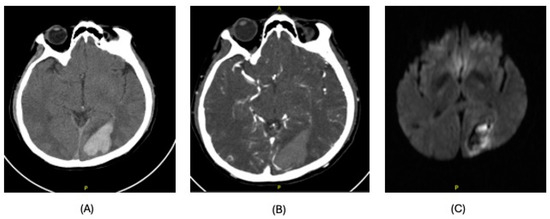

| Diagnosis | Lobar intracranial hemorrhage (ICH) | Basal Ganglia ICH | Lobar ICH | Embolic ischemic stroke (IS) | Embolic IS | |

| Clinical Syndrome | Left headache, right hemianopia | Persistent drowsiness post-OLT, GCS E1VTM2, dilated right pupil | Headache, right hemiparesis, right lower limb sensory deficits | Aphasia | Altered mental status, right gaze preference, left flaccid paralysis | |

| Imaging | CT scan | CT scan | CT scan MRI CT angiography | CT scan MRI MR angiography | CT scan CT angiography MRI | |

| Findings | CT: Left occipital intraparenchymal hematoma Volume: 15 mL | CT: Large right frontal temporal parenchymal hematoma, severe surrounding mass effect with leftward midline shift, right uncal herniation Volume: 93.5 mL | CT: Right frontoparietal parenchymal hematoma with locoregional mass effect, rightward midline shift Volume: 25 mL | CT: Left occipital infarct Transcranial doppler: 2 spontaneous emboli, more than 100 high intensity transient signals (HITS) in bilateral middle cerebral arteries (MCAs) after agitated saline | CT: Right parietal lobe hypodensity Transcranial doppler: more than 300 HITS in bilateral MCAs after agitated saline | |